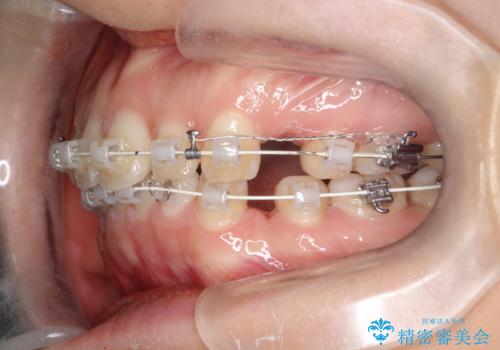

- 矯正装置

- 審美装置

- 治療期間

- 2年

- 治療回数

- 10-30回